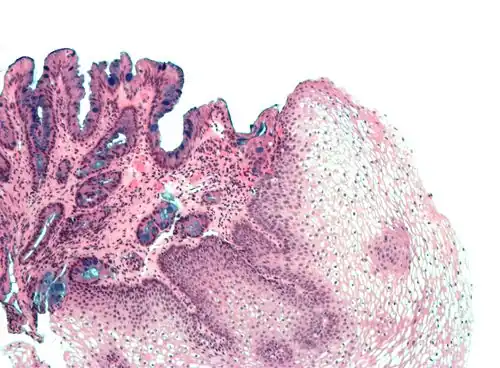

Both macroscopic (from endoscopy) and microscopic positive findings are required to make a diagnosis. Barrett's esophagus is marked by the presence of columnar epithelia in the lower esophagus, replacing the normal squamous cell epithelium—an example of metaplasia. The secretory columnar epithelium may be more able to withstand the erosive action of the gastric secretions; however, this metaplasia confers an increased risk of adenocarcinoma.[15]

Intestinal metaplasia

The presence of goblet cells, called intestinal metaplasia, is necessary to make a diagnosis of Barrett's esophagus. This frequently occurs in the presence of other metaplastic columnar cells, but only the presence of goblet cells is diagnostic. The metaplasia is grossly visible through a gastroscope, but biopsy specimens must be examined under a microscope to determine whether cells are gastric or colonic in nature. Colonic metaplasia is usually identified by finding goblet cells in the epithelium and is necessary for the true diagnosis.

Many histologic mimics of Barrett's esophagus are known (i.e. goblet cells occurring in the transitional epithelium of normal esophageal submucosal gland ducts, "pseudogoblet cells" in which abundant foveolar [gastric] type mucin simulates the acid mucin true goblet cells). Assessment of relationship to submucosal glands and transitional-type epithelium with examination of multiple levels through the tissue may allow the pathologist to reliably distinguish between goblet cells of submucosal gland ducts and true Barrett's esophagus (specialized columnar metaplasia). The histochemical stain Alcian blue pH 2.5 is also frequently used to distinguish true intestinal-type mucins from their histologic mimics. Recently, immunohistochemical analysis with antibodies to CDX-2 (specific for mid and hindgut intestinal derivation) has also been used to identify true intestinal-type metaplastic cells. The protein AGR2 is elevated in Barrett's esophagus[17] and can be used as a biomarker for distinguishing Barrett epithelium from normal esophageal epithelium.[18]